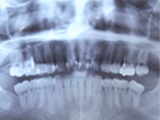

STEP1 診査・診断(レントゲン撮影)

歯周病は1本の歯だけではなく、お口の中にある全ての歯を支えている歯周組織を破壊していく病気です。まずレントゲン撮影をし、歯槽骨(歯を支える顎の骨)が現在どの程度失われているか確認します。それから、歯周ポケットを測定し、歯周病の進行程度を全ての歯について調べていきます。